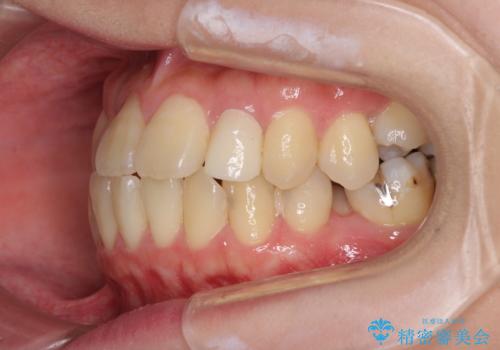

- 下顎の歯が舌側に倒れていることと、前歯の咬み合わせの不具合を気にして来院された患者様です。

受け口傾向の口元であるため、下顎左右小臼歯各1歯を抜歯して歯列を整えることとしました。

前歯には治療中の仮歯が装着されていたため、矯正治療後にオールセラミッククラウンにて補綴治療を行うこととしました。